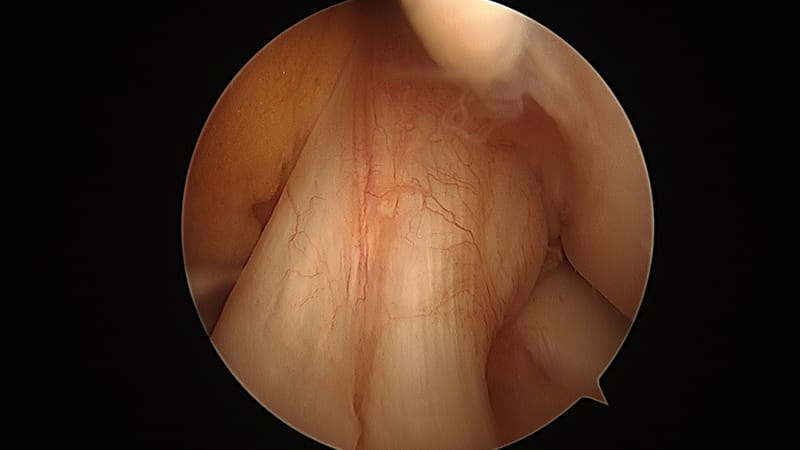

Per i pazienti che presentano una lesione del LCA di grado II o III e che hanno una lacerazione del menisco, esiste un rischio molto più elevato di sviluppo di artrosi in futuro. Per questo motivo di solito si consiglia di eseguire una riparazione, ove possibile, del menisco in associazione ad una ricostruzione del LCA e di eseguire le ricostruzioni del LCA in pazienti giovani o altrimenti attivi e in quasi tutti i pazienti che riferiscono instabilità con attività di torsione o rotazione. La tecnica della chirurgia LCA è cambiata radicalmente negli ultimi anni. Gli innesti di ricostruzione del crociato anteriore eseguiti anni fa erano posizionati più centralmente sia sulla tibia che sul femore - la ricerca ha dimostrato che molti di questi pazienti hanno continui problemi con instabilità di rotazione. Questo problema è stato riconosciuto attraverso un'ampia ricerca clinica e biomeccanica e la tecnica chirurgica è cambiata in cui i tunnel di ricostruzione sono ora posizionati in modo più anatomico per fornire una migliore stabilità al ginocchio, soprattutto per le rotazioni.